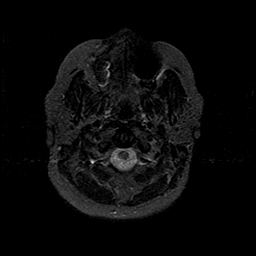

MR Study #1 -- Slice #4